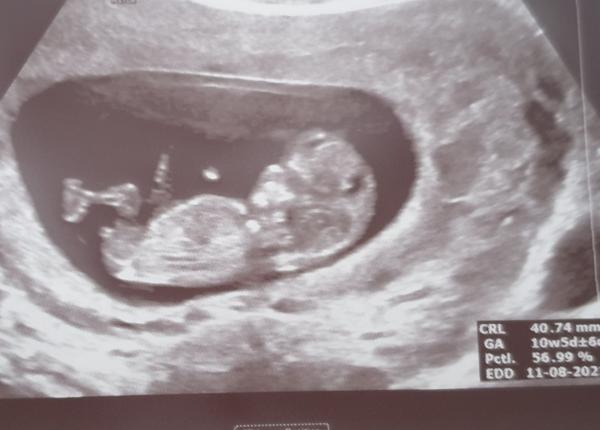

@mikejla_a doktor mi zatím nerekl nic, když jsme koukali poprve, tak ten hrbolek mířil uplne dolu a byl delsi až jsem se divila a pak na to koukal z jiného pohledu a vypadalo to jak na te fotce,tak už opravdu nevím. První fotka byla tato,ale to byl asi 11 tyden.

@janagranada on je jakoby nejjistejsi az kolem toho 13tt,protoze driv můžou mit i kluci hrbolek rovne a pak se zvedne.

@janagranada já bych počkala min do 20tt, do té doby jsou to prý jen odhady. Dobří doktoři to samozřejmě umí odhadnout i takto brzo, protože to mají nadívané. Každopádně bych ještě závěry nedělala 🙂